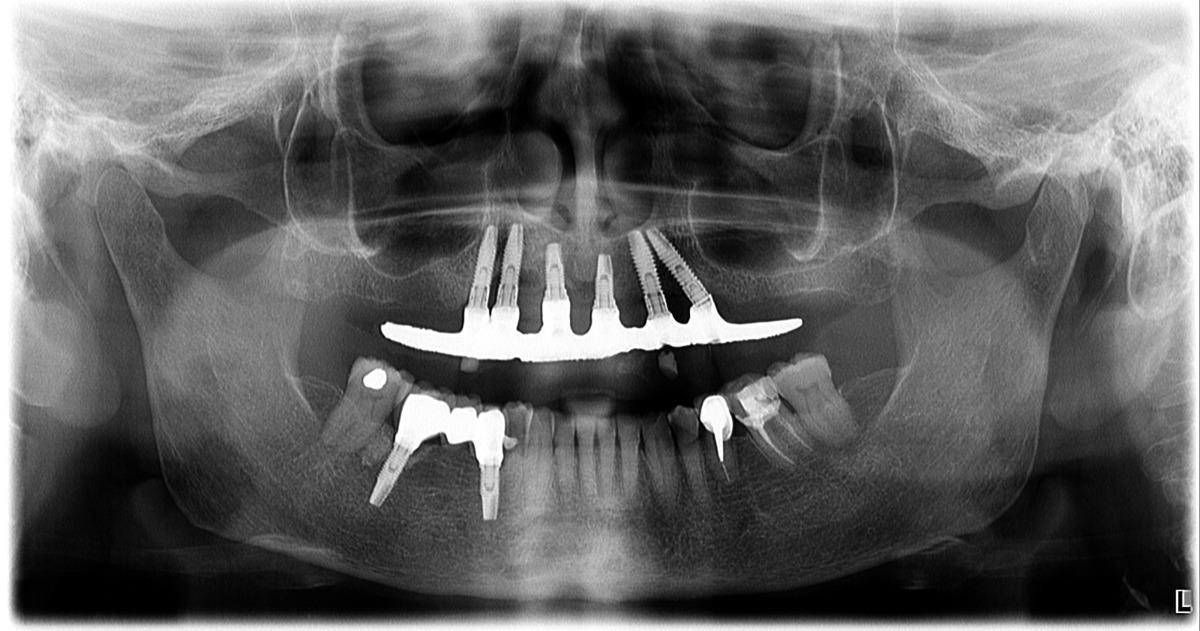

PRÓTESE TOTAL FIXA EM IMPLANTES